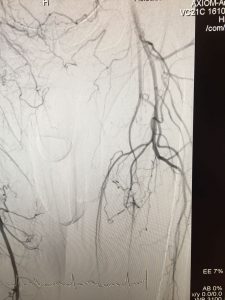

Girişimsel yöntemlerin hepsi anjiografi salonunda, lokal anestez altında ve herhangi bir kesi yapılmadan uygulanır. Hastanede yatış süresi ve iyileşme süreci, cerrahi tedaviye göre daha kısadır. Bununla birlikte işlem yapılan damarlarda erken veya geç dönemde tekrar darlık oluşma veya tıkanma riski bulunmaktadır.

Balon Anjioplasti

• Balon Anjioplasti : Damar içinde görülen darlıkların tedavisinde etkin bir şekilde kullanılan yöntemdir. Damarda daralmaya sebep olan plakların damar duvarına yapıştırılması esasına dayanır. İlaçlı veya ilaçsız balonlarla uygulanabilir. İlaçlı balonlar, mekanik etkilerinin yanında içerdikleri farmakolojik ajanların, damar duvarında oluşturdukları antiinflamatuar (iltihabi süreci engelleme) etkileri nedeni ile ilaçsız balonlara oranla daha etkindirler.